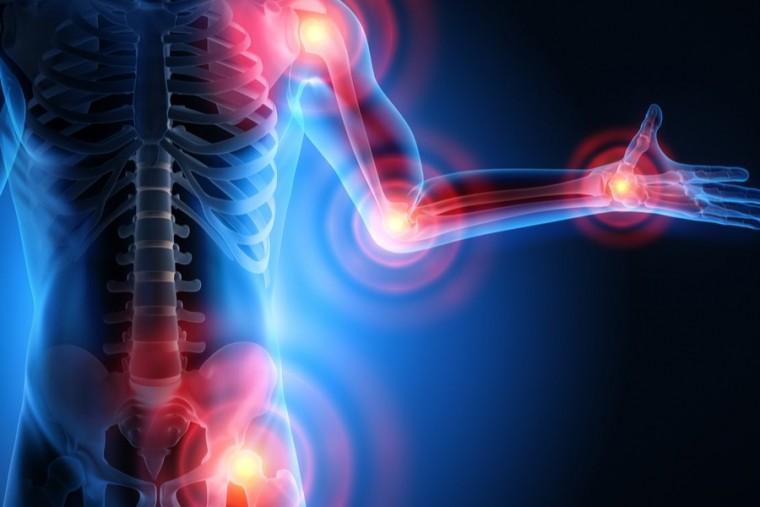

ఆర్థరైటిస్పై అవగాహన పెరగడం వల్ల సమస్యలను అధిగమించవచ్చని వైద్యులు చెబుతున్నారు

Publish : Fri, Oct 11, 2024, 08:37 PM